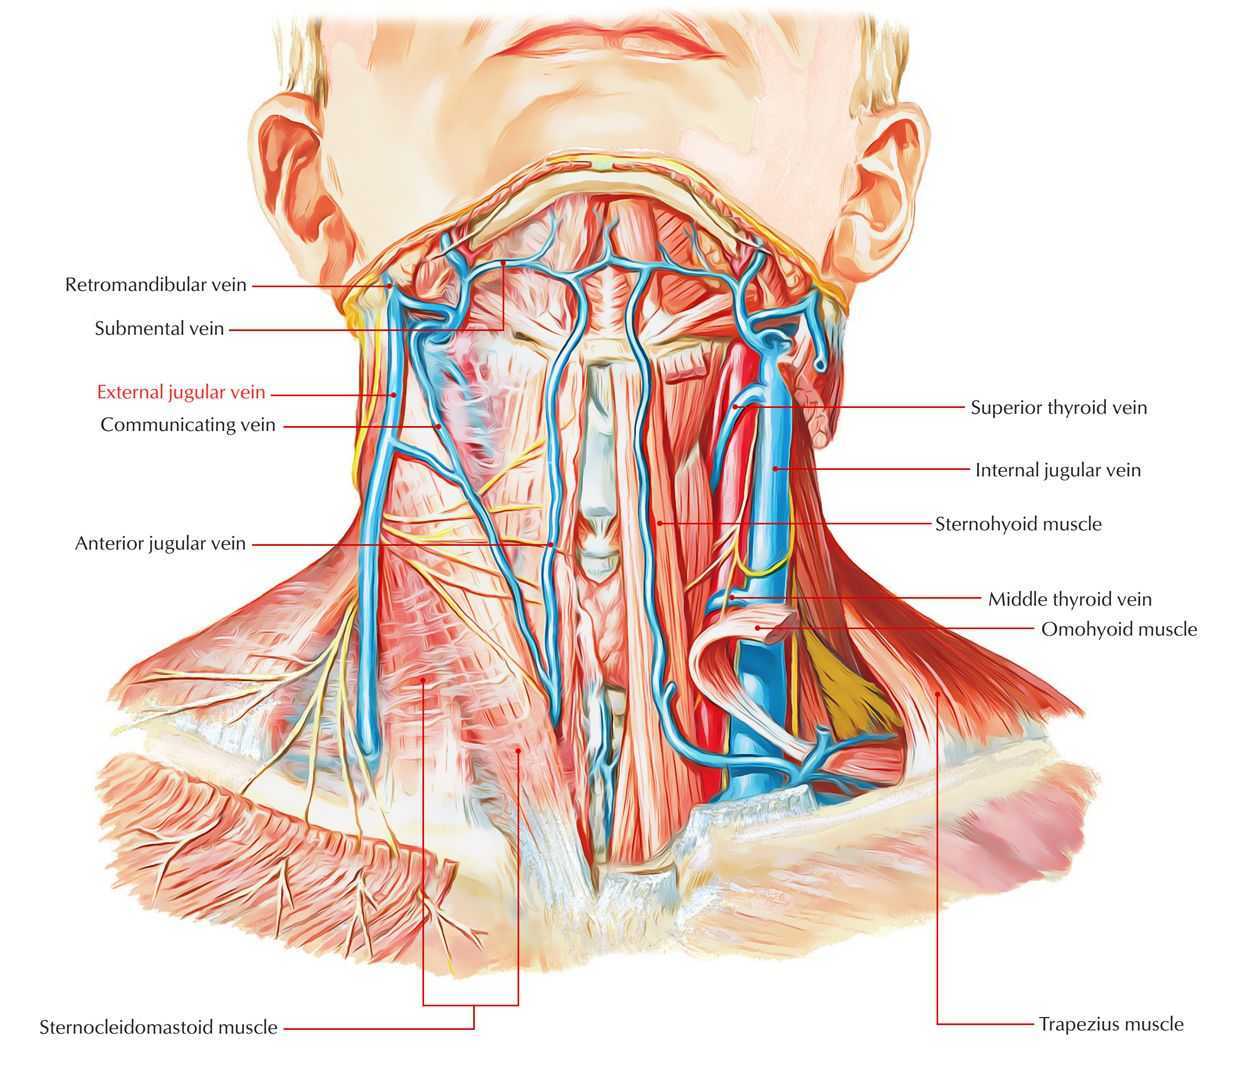

Анатомия внутренней яремной вены: КТ изображения